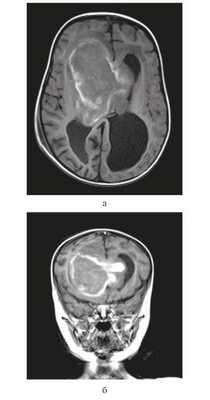

Девочка в возрасте 11 мес. Заболела остро, после перенесенной легкой черепно-мозговой травмы — упала с высоты собственного роста, после чего стала утрачивать приобретенные навыки: перестала стоять, сидеть, появилась вялость, адинамия, срыгивания. При МРТ головного мозга выявлена гигантская опухоль боковых и III желудочков, окклюзионная гидроцефалия (рис. 1).

Рисунок 1. Магнитно-резонансные томограммы грудного ребенка 11 мес с гигантской внутрижелудочковой опухолью. а — Т1 с контрастным усилением, аксиальный срез, б — Т1 с контрастным усилением, фронтальный срез.